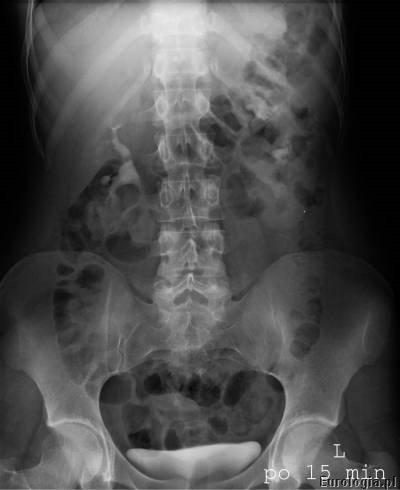

Kolejną fazą w badaniu jest faza wydzielnicza, w czasie której uwidocznione zostają układ kielichowo- miedniczkowy i moczowody. Urolog na podstawie zdjęć urograficznych ocenia nerki i moczowody pod kątem obecności w nich złogów, wad anatomicznych – np. zwężenie połączenia miedniczkowo – moczowodowego lub nowotworów. Nowotwory urothelialne występujące w układzie kielichowo – miedniczkowym lub moczowodzie widoczne są jako ubytki wypełnienia. W przeszłości urografia była podstawową metodą rozpoznawania guzów nerki.

Mocz spływający z układu kielichowo – miedniczkowego moczowodami do pęcherza zakontrastowuje układ moczowy dzięki czemu na zdjęciach rentgenowskich możliwa jest ocena czy spływ jest swobodny, czy utrudniony. W przypadku utrudnionego spływu badanie z reguły pozwala na ocenę miejsca i rodzaju przeszkody.

Urografia wykonywana jest w pracowni rentgenowskiej i trwa około 30 minut. W czasie badania pacjent układany jest w pozycji leżącej na plecach na stole rentgenowskim. Pierwsze zdjęcie wykonane przed podaniem kontrastu nazywane jest zdjęciem przeglądowym nerek i pęcherza, na którym możliwe jest uwidocznienie cieni mogących być uwapnionymi złogami w układzie moczowym. Kolejnym etapem badania jest dożylne podanie kontrastu przez wenflon wkłuty na przedramieniu pacjenta. Po podaniu kontrastu wykonywana jest seria zdjęć rentgenowskich w odpowiednich odstępach czasu. Czasami konieczne jest wykonanie tak zwanych późnych zdjęć urograficznych w sytuacji gdy w standardowym czasie nie uzyskano zakontrastowania układu kielichowo – miedniczkowego lub moczowodu.

Przykładowe badanie urograficzne :